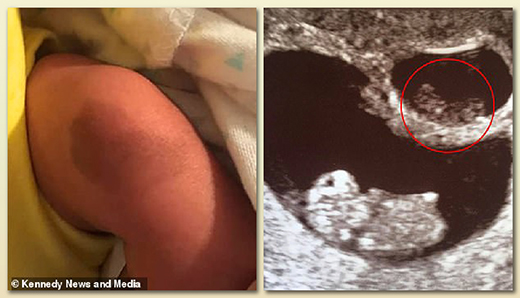

▲ 엄마 자궁 속에서 사라진 쌍둥이의 흔적이 태어난 쌍둥이의 무릎에 남아 있는 모습

[1] 임신 10주 이후 사라진 쌍둥이가 자신의 쌍둥이의 무릎에 붙어서 흔적을 남긴 모습. 영국 데일리메일